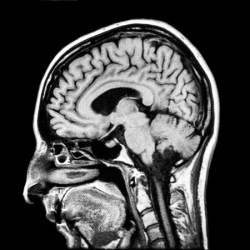

As mentioned above, the study itself highlighted a series of changes in the volume of certain brain regions, and the degree to which these brain regions are connected before and after testosterone treatment. These findings represent an interesting case study of plasticity – hormones such as testosterone (which is naturally occurring in both genders, although to a greater degree in men) are well known to interact with brain development (a nice undergraduate-level overview can be found here), but it’s rare to find an opportunity to able to study these effects in adults. However, quality of the research, which is difficult to assess without a publication to refer to, and the appropriately detailed descriptions of the study itself are not the main issue with the press coverage here.

Again, just to emphasize, these individuals have not undertaken any cognitive test of their multi-tasking skill (although they certainly could have, which would make for some interesting and complementary science) – they have only had brain scans and the scientists have noted changes in regions of the brain which are associated with certain cognitive processes. This is the reverse inference. That something which has not been tested (multi-tasking skill) must have changed based on changes in something which has been measured (the volume and connectivity of certain brain areas). The article in the Telegraph is perhaps the most egregious offender, stating that “They found that qualities more traditionally attributed to women, such as verbal and multitasking skills, diminished, while others increased”.

This might not seem so unreasonable, but it’s a dangerous game to play. For one, logically-speaking, the reverse inference only holds true if brain areas only perform a certain function. They don’t. Secondly, it’s also only appropriate to make reverse inferences if a cognitive process (such as multi-tasking) relies only on a single brain region. It doesn’t. Indeed, almost all parts of our brain have been implicated in a huge range of diverse processes, and almost all cognitive processes call upon a network of ‘regions’. For those of you who want a hands-on demonstration of this, Neurosynth.org is great fun to play about with, allowing you to click on a particular part of the brain and seeing all of the (amazingly diverse) research associated with that region, or examine which brain areas are frequently associated with different cognitive skills (e.g., visuospatial ability).